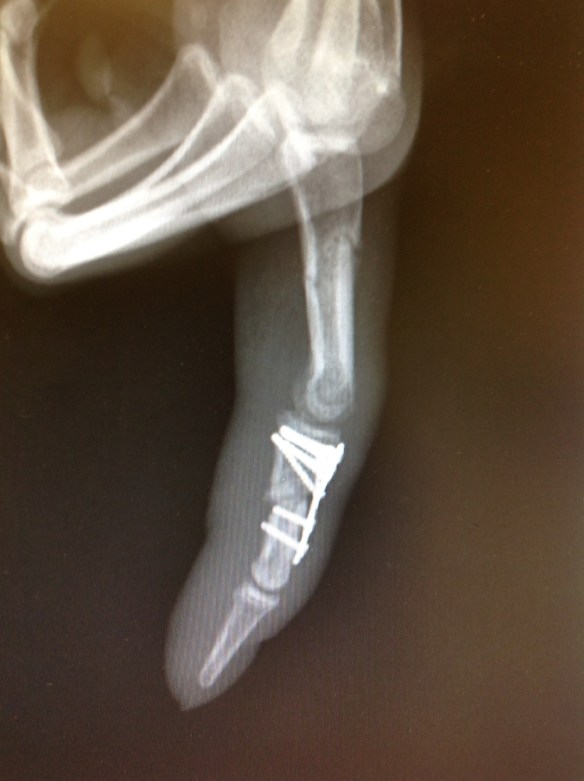

Este es el estado actual a las 9 semanas postoperatorias.